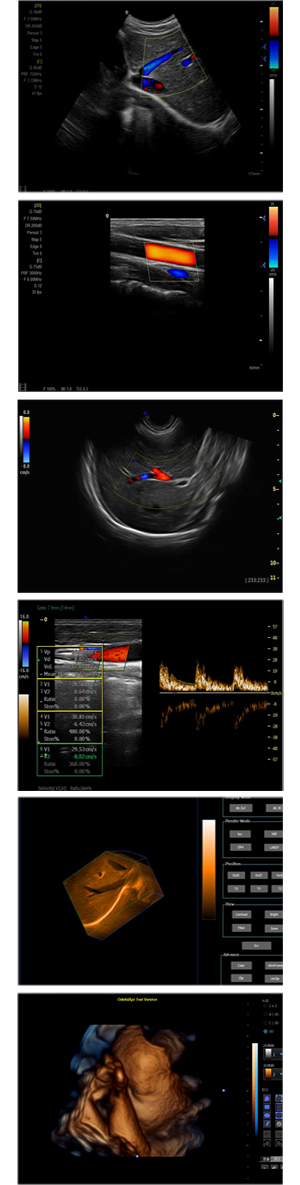

XF-7600型,秉承先鋒彩超技術之精華,擁有高雅大氣的獨特外型,為最新一代應用型數(shù)字彩色多普勒診斷系統(tǒng),魅力與實力相融合??蓮V泛適用于腹部、婦產(chǎn)科、心臟、小器官、乳腺、肌骨及外周血管等諸多方面的診查,讓您在臨床超聲診斷應用領域得心應手,綻放異彩!

● 3D/ 4D成像技術/選配

● 應用于腹部、腎臟、泌尿系統(tǒng)、產(chǎn)科、婦科、盆腔、大動脈、肌肉組織、小器官、乳腺、心臟等

● 能量多普勒成像(PDI)

● 彩色血流量圖(CDE)

● 脈沖頻譜多普勒成像(PW)